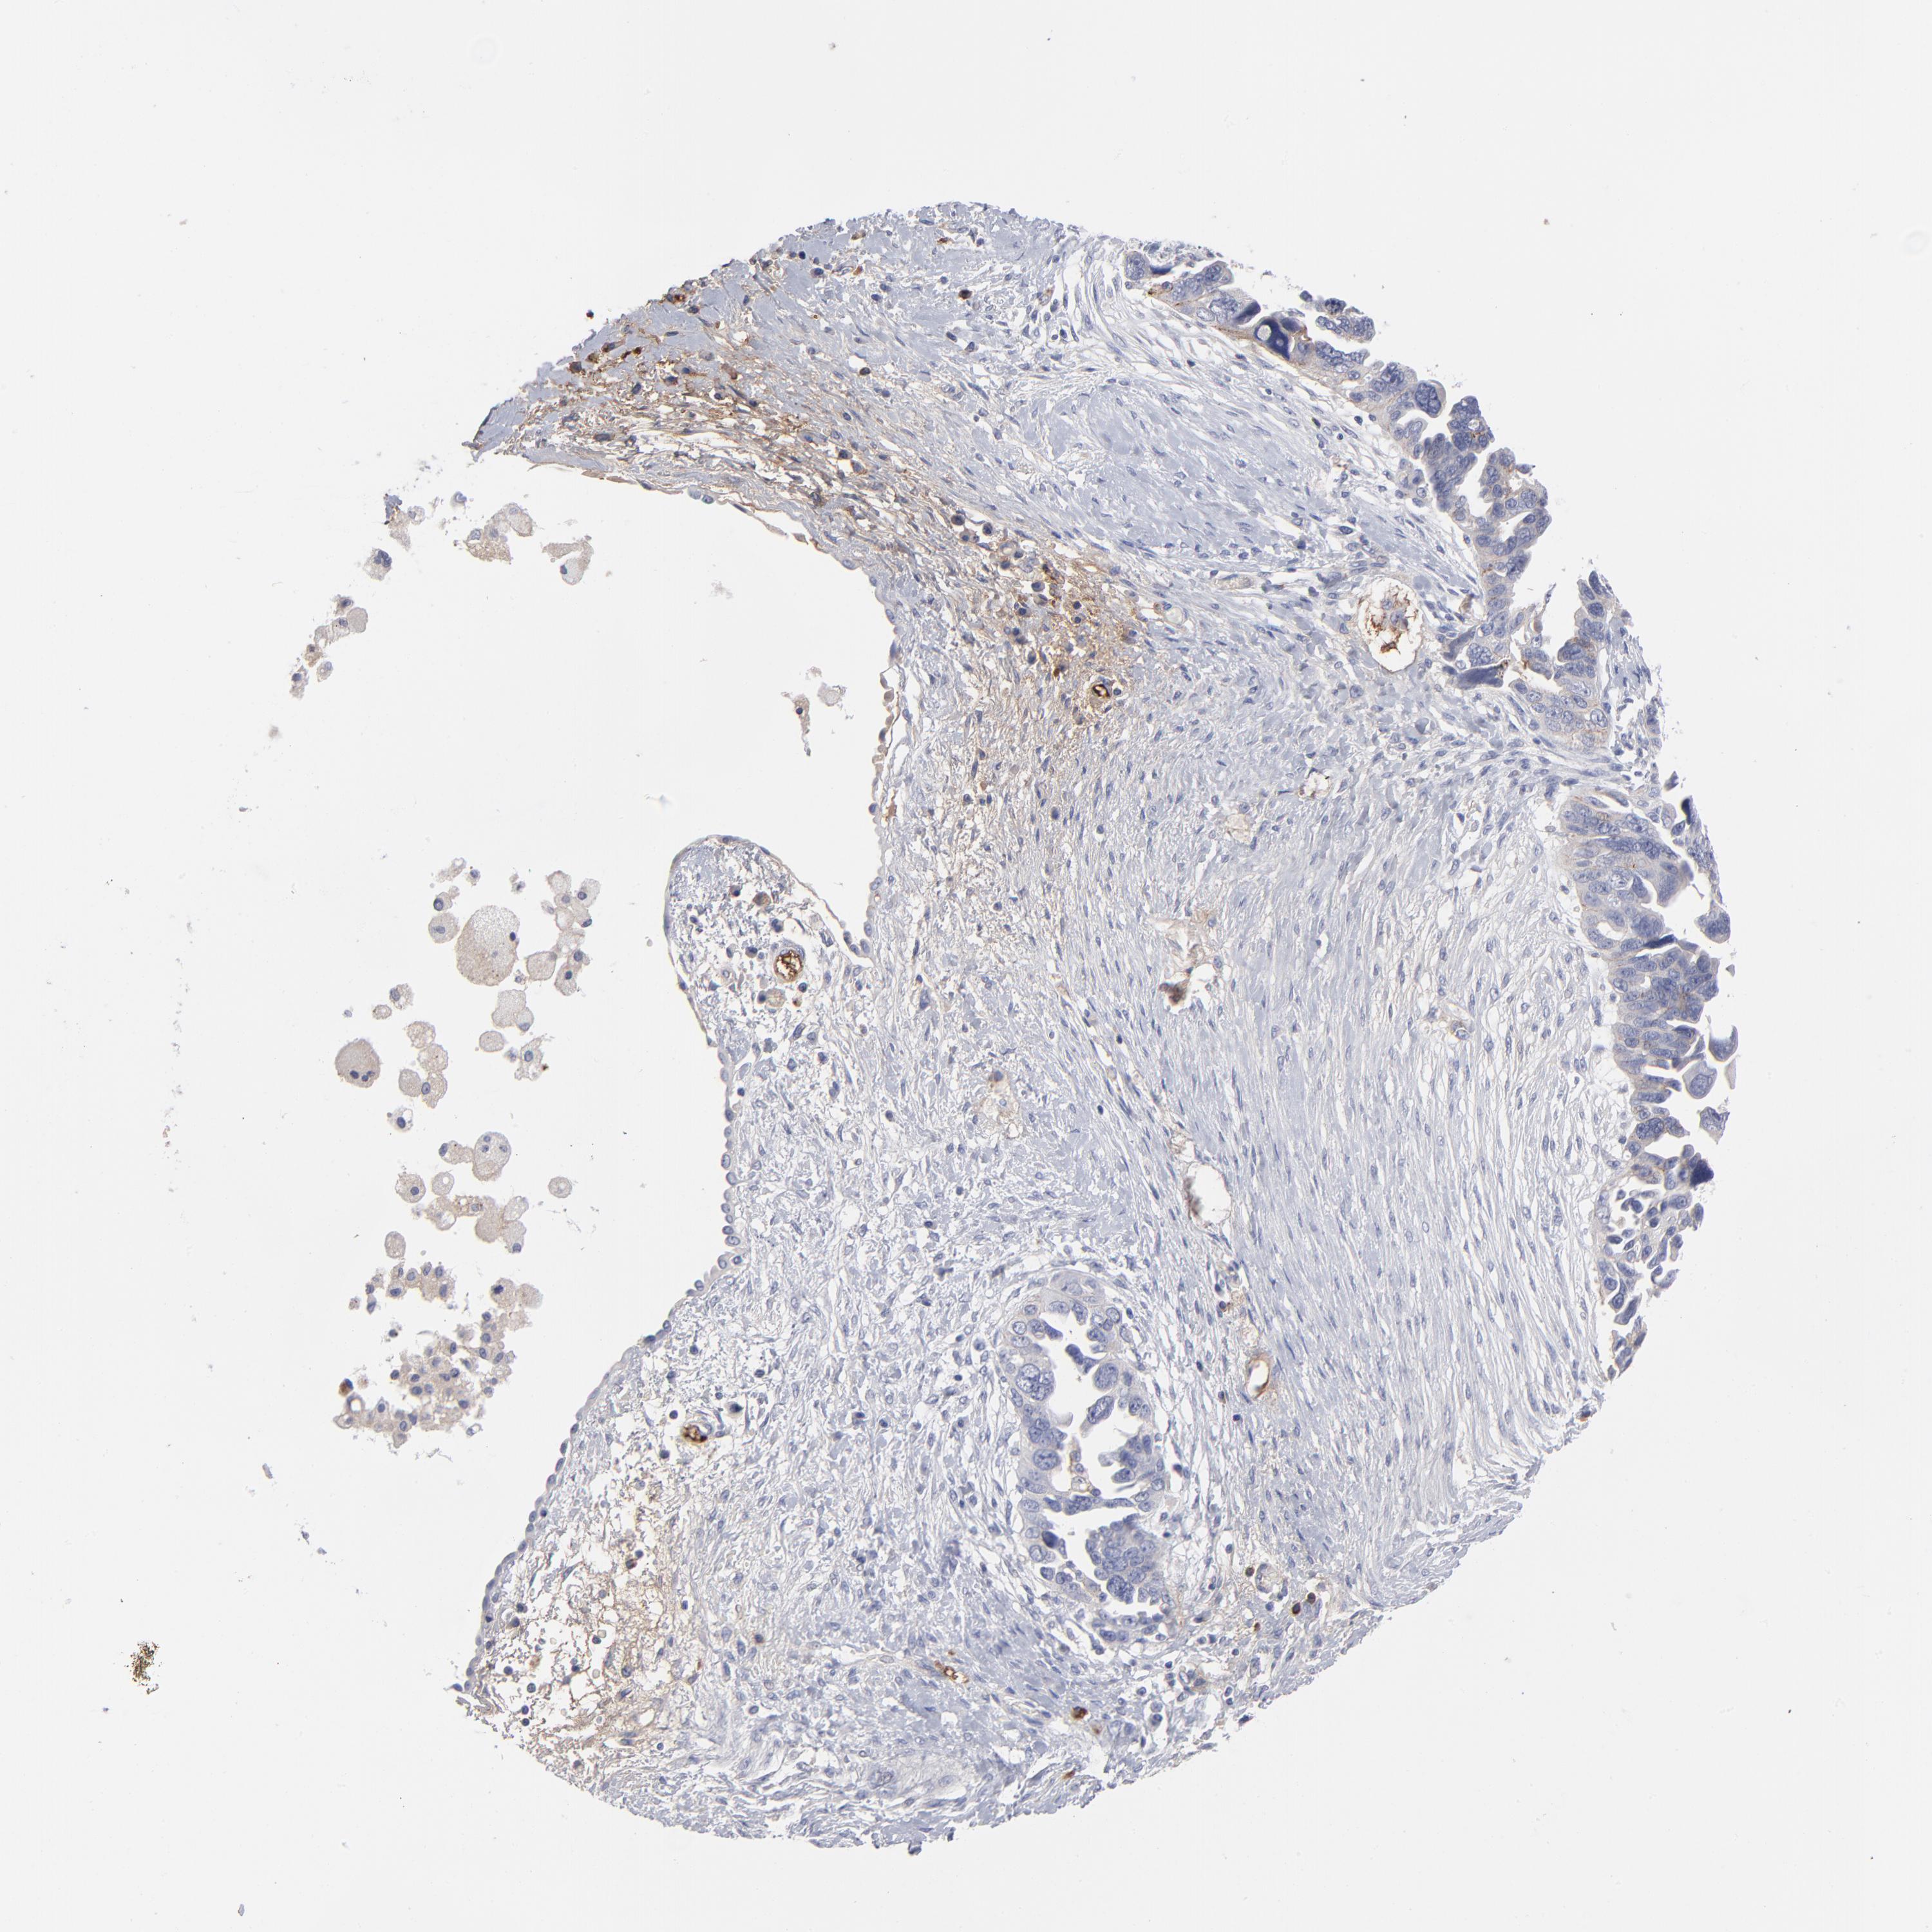

OVARIAN CANCER - Protein expressioni

A mouse-over function shows sample information and annotation data. Click on an image to view it in a full screen mode. Samples can be filtered based on level of antibody staining by selecting one or several of the following categories: high, medium, low and not detected. The assay and annotation is described here.

Note that samples used for immunohistochemistry by the Human Protein Atlas do not correspond to samples in the TCGA dataset.

Antibody stainingi

Antibody staining in the annotated cell types in the current human tissue is reported as not detected, low, medium, or high, based on conventional immunohistochemistry profiling in selected tissues. This score is based on the combination of the staining intensity and fraction of stained cells.

Each image is clickable and will lead to virtual microscopy that enables deeper exploration of all samples and also displays staining intensity scores, fraction scores and subcellular localization as well as patient and tissue information for each sample.

Antibody CAB003795

Staining

Cystadenocarcinoma, mucinous, NOS

Carcinoma, endometroid

Cystadenocarcinoma, serous, NOS